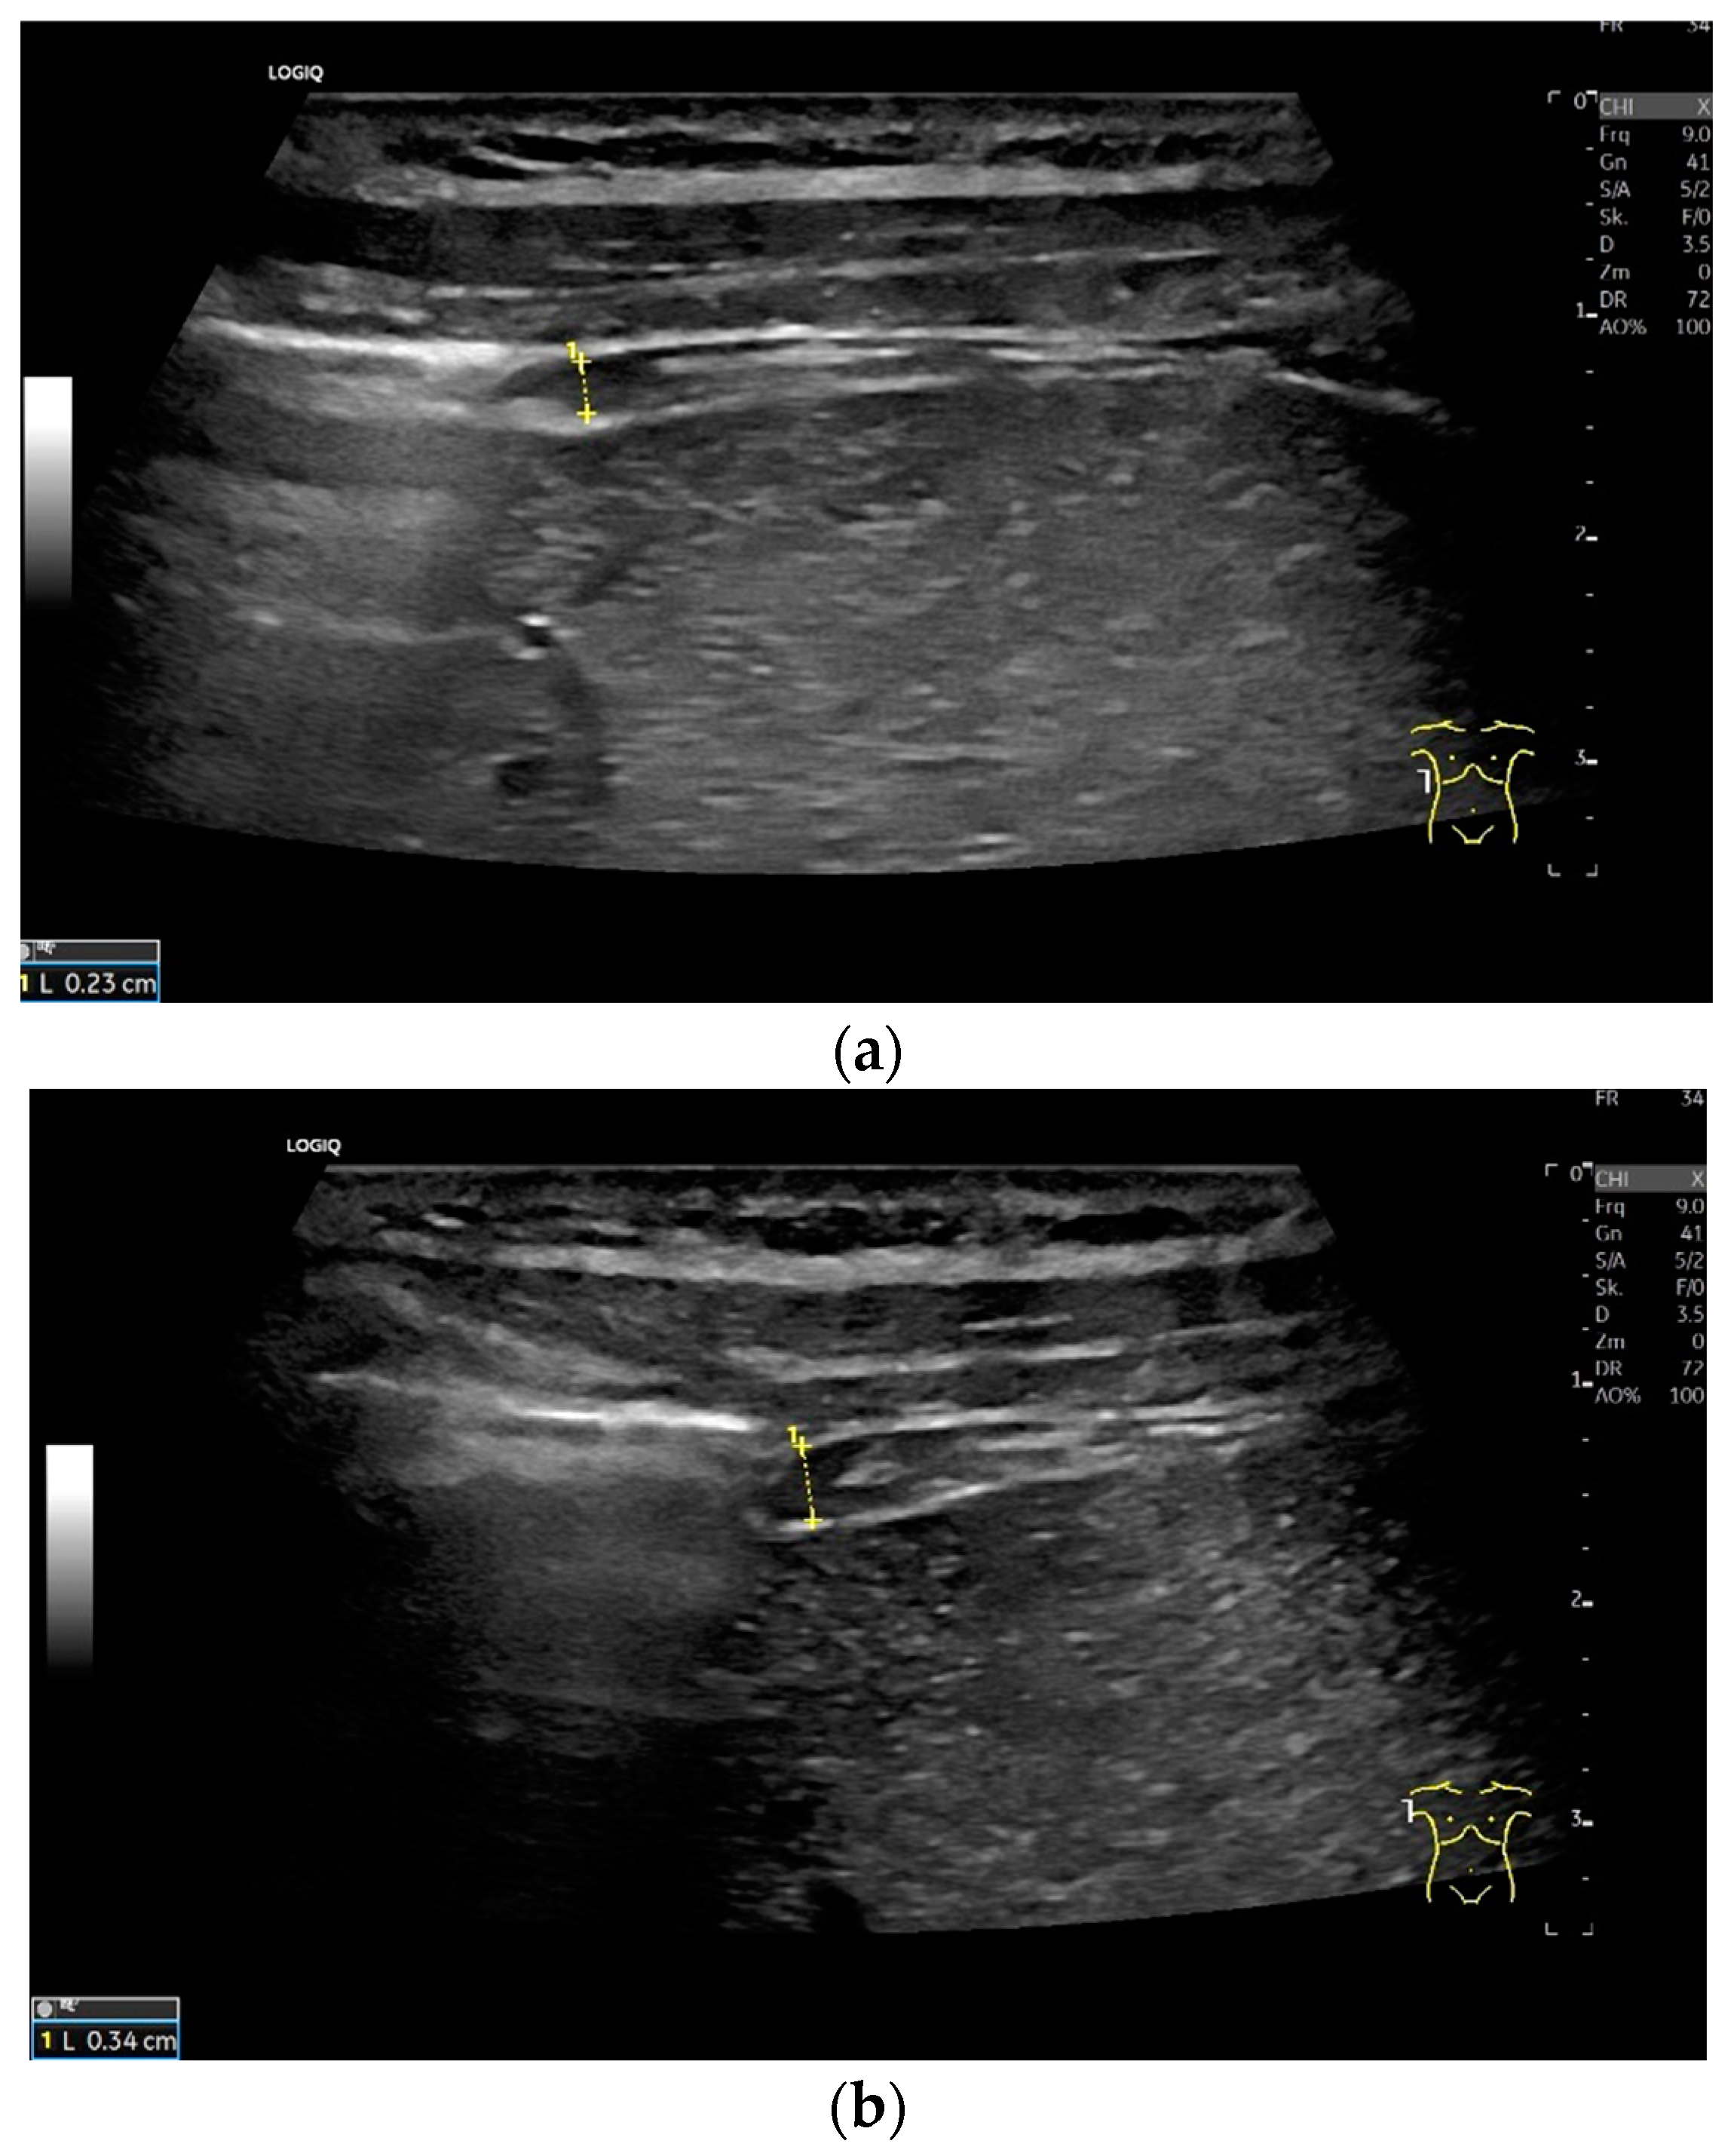

Lateral transducer position in the zone of apposition: The transducer is positioned longitudinally and laterally in the area of the mid-axillary line or slightly ventral to it between the anterior and mid-axillary lines, approximately in the 8th or 10th intercostal space. The diaphragmatic reflex is located on the inner side of the ribs below the pulmonary glide with pulmonary reverberations. This localization of origin of the diaphragm from the inner side of the rib cartilage is referred to as the zone of apposition (Figure 3). As this localization is only a few centimeters below the skin surface, high-resolution linear transducer use is highly recommended. In this position, the diameter of the diaphragm is measured during inspiration and expiration [2,3,4,5] (Figure 4). The thickness of the diaphragm varies, with caudal parts being thicker than cranial parts. The measurement of diaphragm thickness is highly variable depending on the intercostal space chosen, with thickness varying by up to 6 mm between the intercostal spaces [6]. It is therefore important to select the same position for comparable measurements and, if necessary, to mark the location for the transducer position [7]. Obesity limits assessment of the diaphragm [2].

To assess the diaphragm and its function, the diaphragm’s thickness, contraction and excursion are determined. Diaphragm thickness is mainly measured in the zone of apposition and excursion in the subcostal position. The diaphragm thickness is measured at end-expiratory (Tendexpir) and end-inspiratory (Tendinspir) points. Expiratory and inspiratory measurements should be taken with exactly the same transducer position. The measurement is taken at the outer edges of the hypoechoic muscle and at an angle of 90° to the diaphragm’s surface (Figure 4).